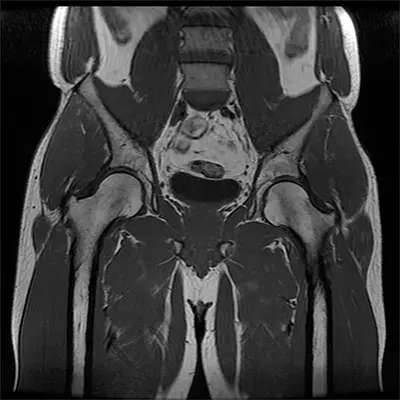

- MRI: Detects soft tissue damage, including the gluteus medius tendon and surrounding structures